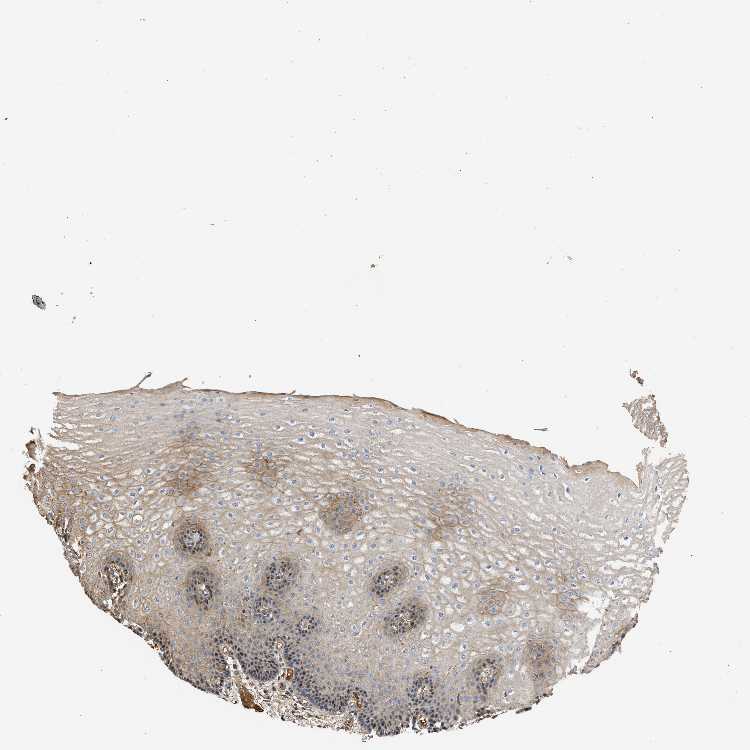

ESOPHAGUS - Antibody stainingi

Antibody staining in the annotated cell types in the current human tissue is reported as not detected, low, medium, or high, based on conventional immunohistochemistry profiling in selected tissues. This score is based on the combination of the staining intensity and fraction of stained cells.

Each image is clickable and will lead to virtual microscopy that enables deeper exploration of all samples and also displays staining intensity scores, fraction scores and subcellular localization as well as patient and tissue information for each sample.

Antibody HPA017983

Squamous epithelial cells Medium